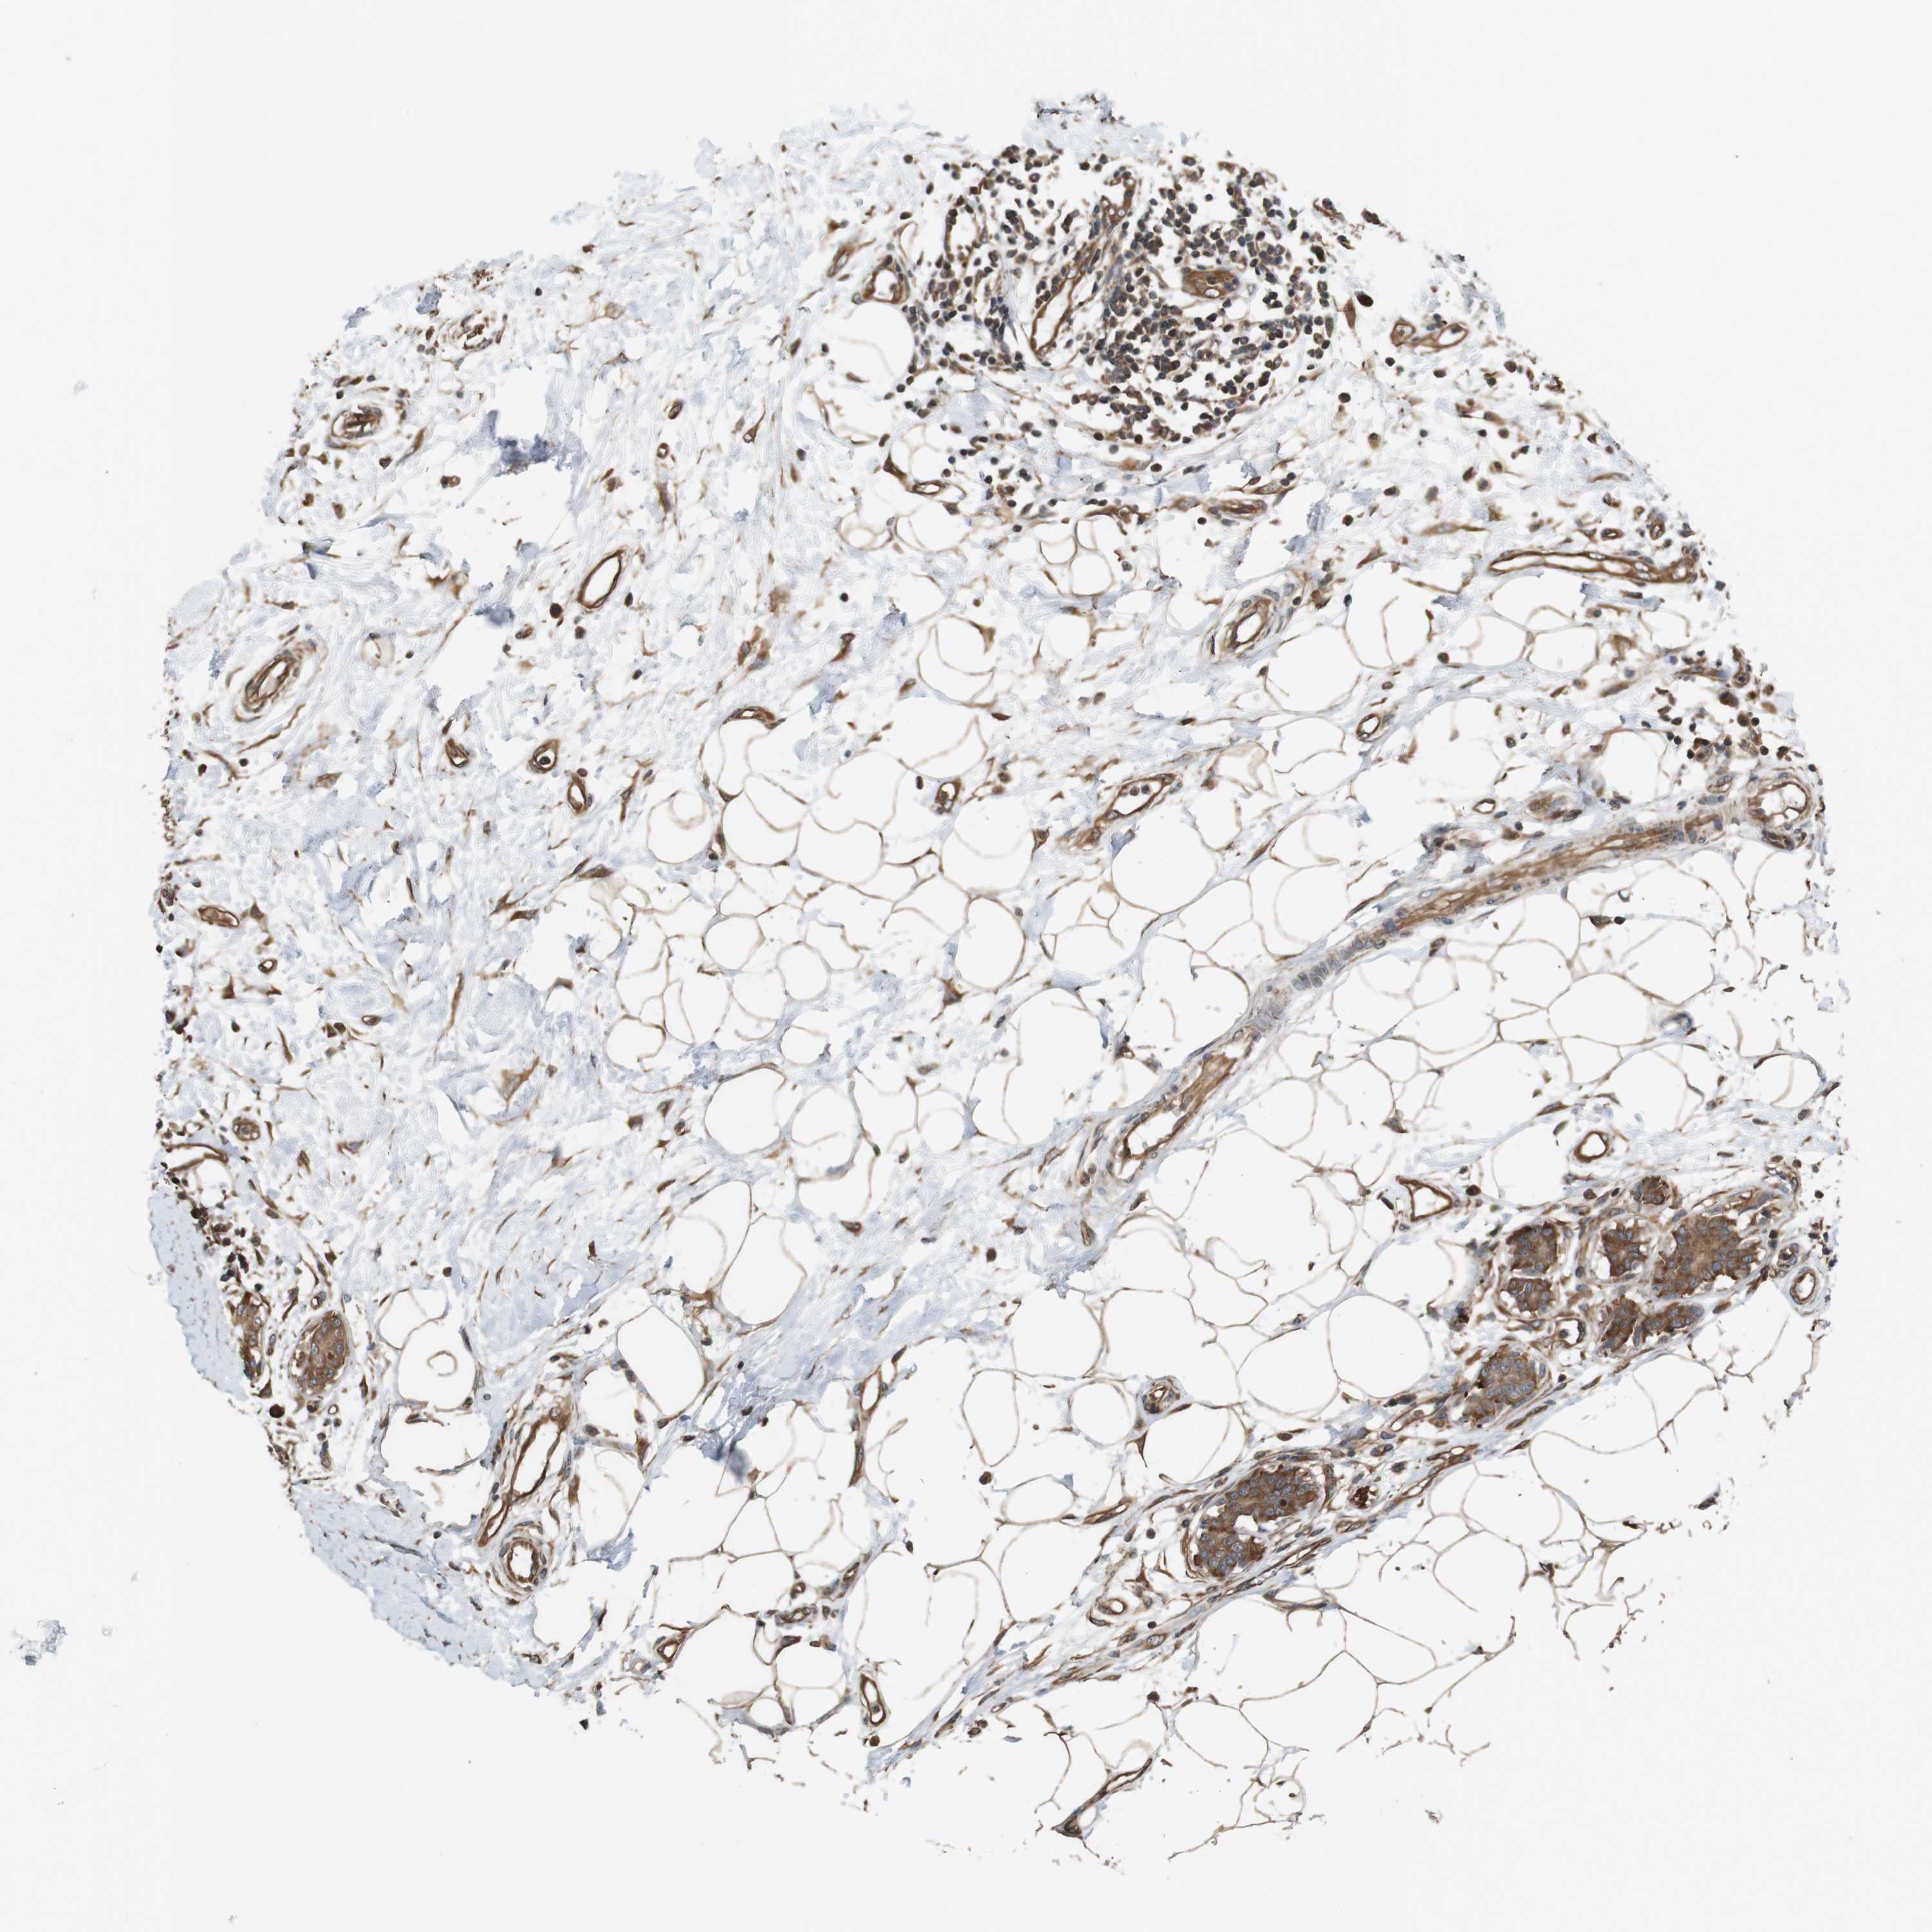

BRCA TCGA BRCA VALIDATION PROTEIN EXPRESSION

Breast cancer

Human cancer